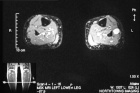

50 year old female with painful mass in left leg for one month

Zoom image: Radiological image Radiological image.